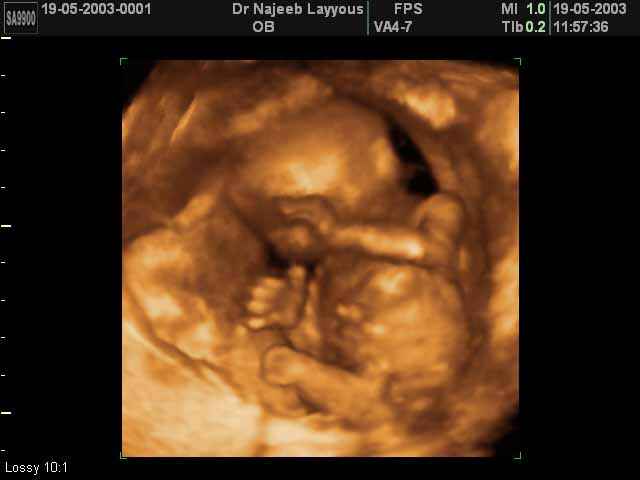

- Fetal Behavior Ultrasound Photos

3D Second Trimester Ultrasound Scan Photos-second part of pregnancy | Dr N Layyous